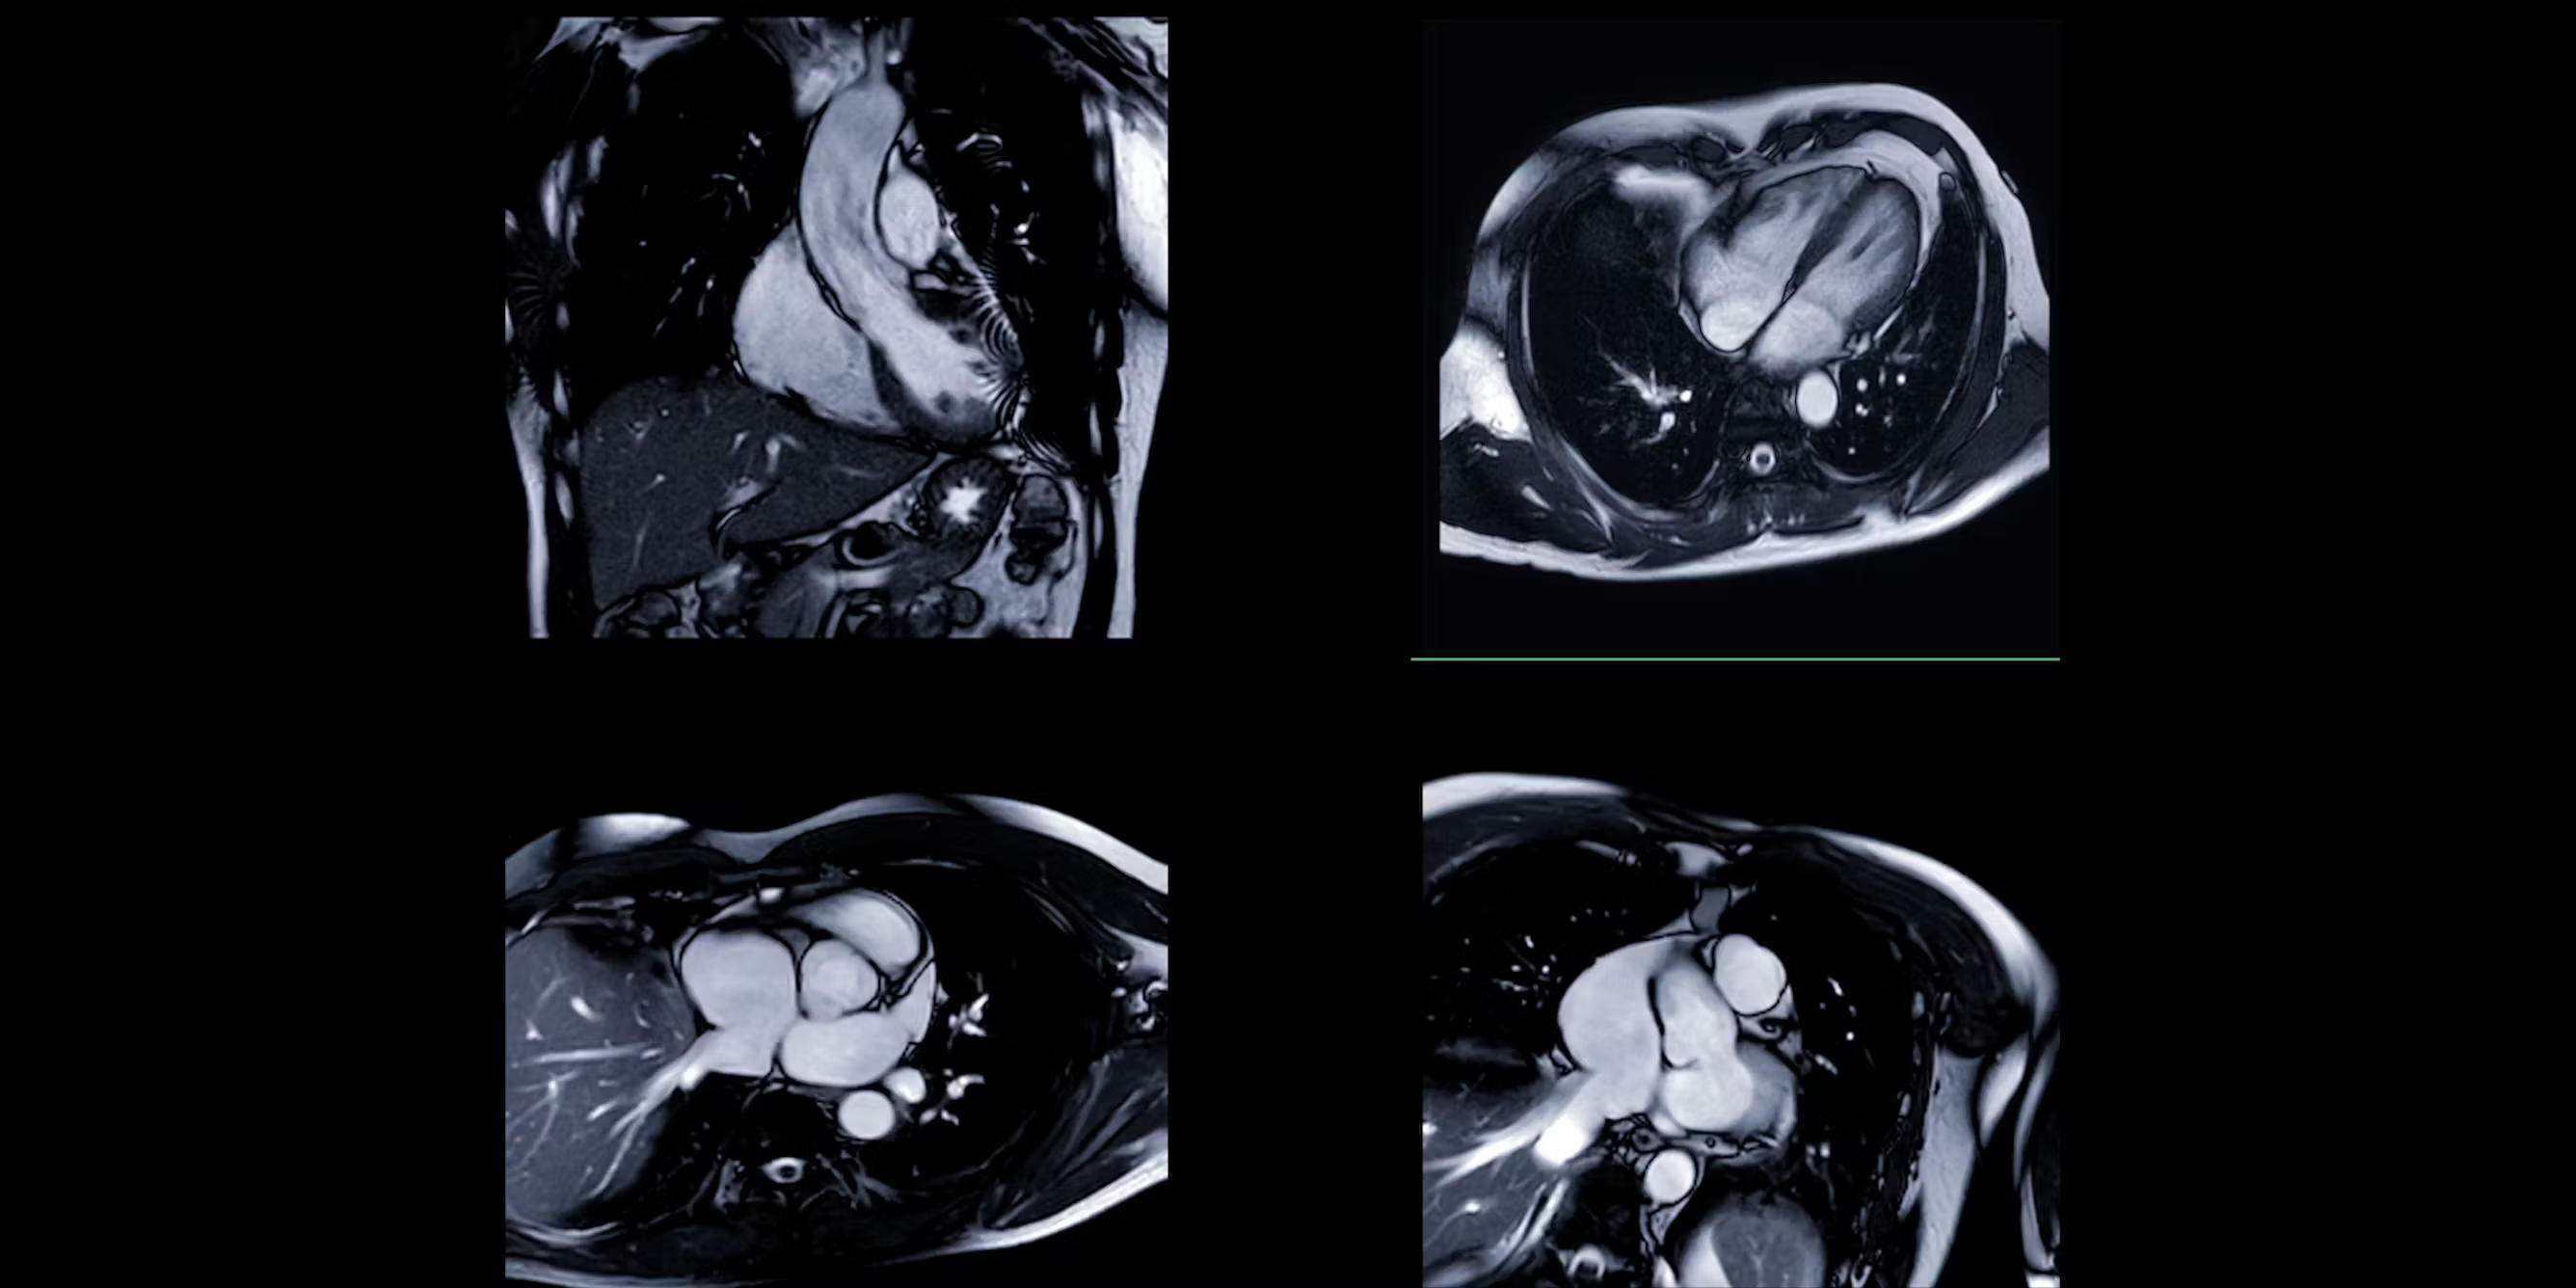

My recent study, which I conducted with colleagues, found that an AI model could guess whether a patient identified as Black or white from heart images with up to 96% accuracy – despite no explicit information about racial categories being given.

In the heart scan study, researchers found that the AI model wasn’t actually focusing on the heart itself, where there were few visible differences linked to racial categories. Instead, it drew information from areas outside the heart, such as subcutaneous fat as well as image artefacts – unwanted distortions like motion blur, noise, or compression that can degrade image quality. These artefacts often come from the scanner and can influence how the AI interprets the scan.

In this study, Black participants had a higher-than-average BMI, which could mean they had more subcutaneous fat, though this wasn’t directly investigated. Some research has shown that Black individuals tend to have less visceral fat and smaller waist circumference at a given BMI, but more subcutaneous fat. This suggests the AI may have been picking up on these indirect racial signals, rather than anything relevant to the heart itself.